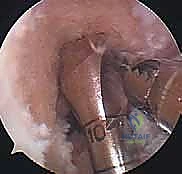

تقنيات جراحة إعادة بناء الرباط الصليبي الأمامي وأنواع الطعوم

لا يمكن خياطة الرباط الصليبي الأمامي المتمزق (إلا في حالات نادرة جداً لتمزقات معينة عند نقطة الاتصال العظمي). لذلك، يجب "إعادة بناء" (Reconstruction) الرباط باستخدام نسيج بديل يُسمى "الطعم" (Graft).

اختيار نوع الطعم هو قرار مشترك بين المريض والأستاذ الدكتور محمد هطيف، بناءً على عمر المريض، مستوى نشاطه، ومهنته.

- الطعم الذاتي من أوتار المأبض (Hamstring Autograft):

- يتم أخذ وترين من خلف الفخذ (Gracilis و Semitendinosus) وطيّهما ليشكلا طعماً رباعي أو خماسي الحزم.

خطوات العملية الجراحية بالتفصيل مع الأستاذ الدكتور محمد هطيف

تُجرى العملية تحت التخدير النصفي أو الكلي، وتستغرق عادةً من ساعة إلى ساعة ونصف. الدقة في هذه الخطوات هي ما يميز الخبير عن غيره.

الخطوة الأولى: الفحص بالمنظار الجراحي 4K

يستخدم الدكتور